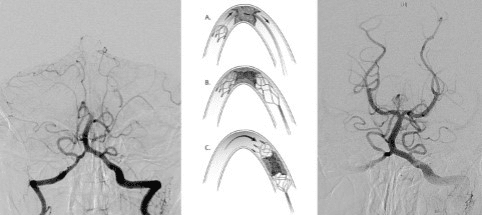

Voor en na verwijderen van een bloedstolsel uit de arteria basilaris (mechanische trombectomie) bij een acute stroke.

Intra-arteriële trombectomie

Als het infarct korter dan zes uur geleden heeft plaatsgevonden, komt u mogelijk in aanmerking voor intra-arteriële trombectomie (IAT). Bij deze behandeling verwijdert de arts via een katheter (een dun slangetje) het stolsel uit het bloedvat. De arts brengt de katheter in via de slagader in uw lies. Deze katheter wordt omhoog gevoerd tot in uw hoofd. Daarna brengt de arts via de katheter een stent (stenttriever) naar uw hoofd om het stolsel eruit te trekken. Soms kan de arts het stolsel eruit zuigen via een katheter.

Met behulp van een CT-scan van de bloedvaten (CTA) bekijkt de arts of u in aanmerking komt voor deze behandeling. De trombectomie is alleen mogelijk wanneer het bloedstolsel dat het infarct veroorzaakt zich in de grotere bloedvaten bevindt. Soms wordt deze behandeling onder narcose uitgevoerd.